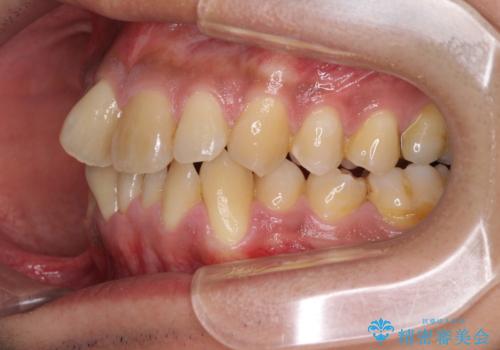

上顎の狭い歯列をインビザラインで拡大

- 上下前歯の叢生を気にして来院された患者様です。

奥歯はクロスバイトとなっているので上顎は側方拡大を行いつつ、上下全体の叢生をインビザラインにより改善することとしました。

治療途中でクリーニングやホワイトニングを行い、歯列が整うと同時に明るい口元となりました。